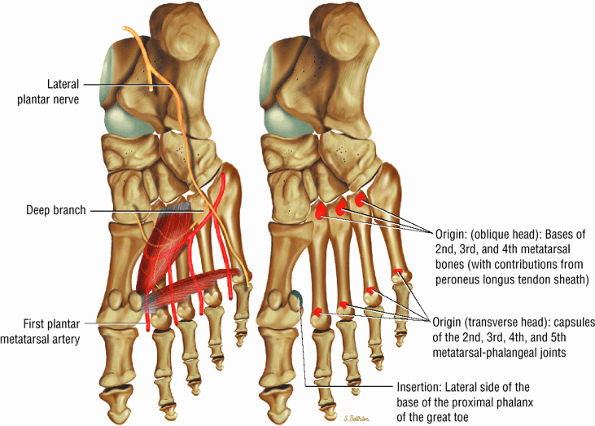

The muscles of the foot are the extensor digitorum brevis (Fig. 5.14), the abductor hallucis (Fig. 5.15), the flexor digitorum brevis (Fig. 5.16), the abductor digiti minimi (Fig. 5.17), the quadratus plantae (Fig. 5.18), the lumbricals (Fig. 5.19), the flexor hallucis brevis (Fig. 5.20), the adductor hallucis (Fig. 5.21), the flexor digiti minimi brevis (Fig. 5.22), the dorsal interossei (Fig. 5.23), and the plantar interossei muscles (Fig. 5.24).

FIGURE 5.21 ● ADDUCTOR HALLUCIS The adductor hallucis has two heads and forms a conjoined tendon. The adductor hallucis adducts the great toe and assists in its flexion.

FIGURE 5.22 ● FLEXOR DIGITI MINIMI BREVIS The flexor digiti minimi brevis flexes the little toes.